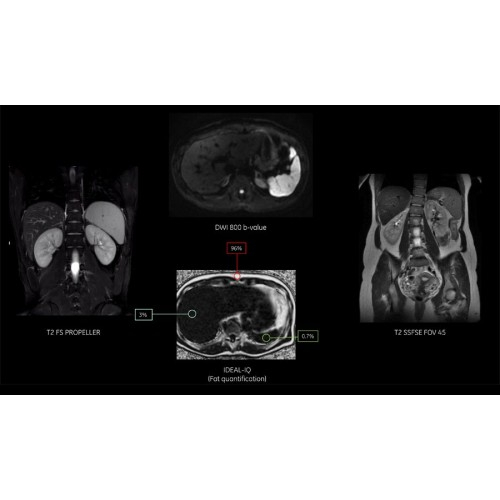

МРТ аппарат GE SIGNA Voyager 1.5T позволяет проводить полный спектр магнитно-резонансных исследований, включая нейровизуализацию, исследования опорно-двигательного аппарата, органов брюшной полости и малого таза, а также специализированные кардиологические программы.

• Обследования органов брюшной полости и малого таза